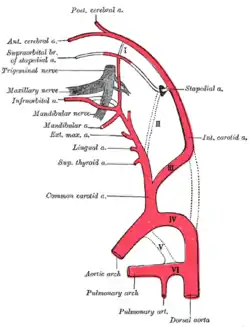

Diagram showing the origins of the main branches of the carotid arteries. | |